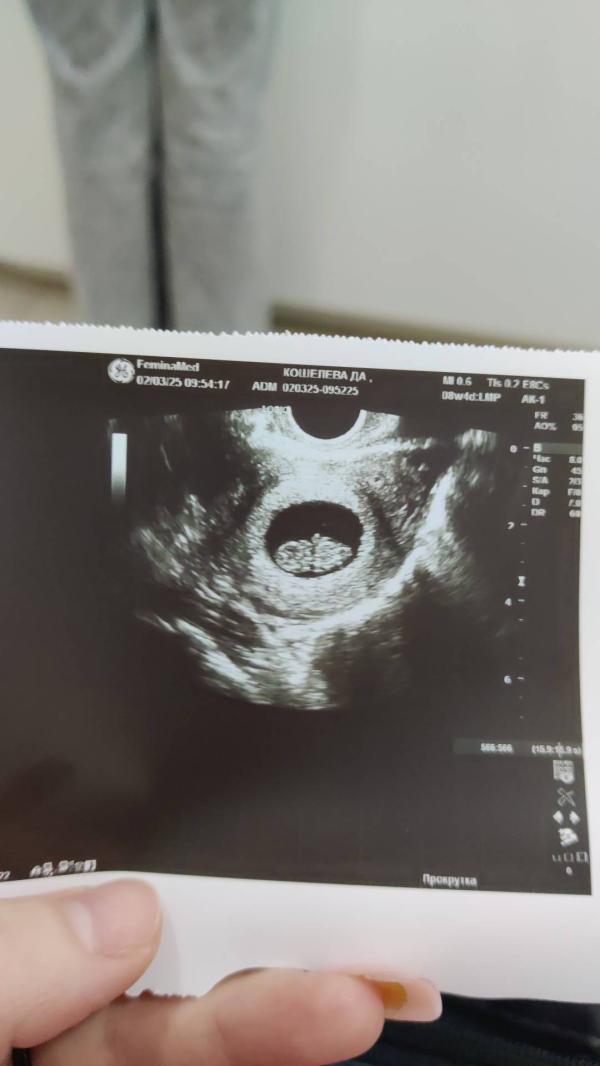

Первое узи, первый скрининг и казалось ещё столько времени....